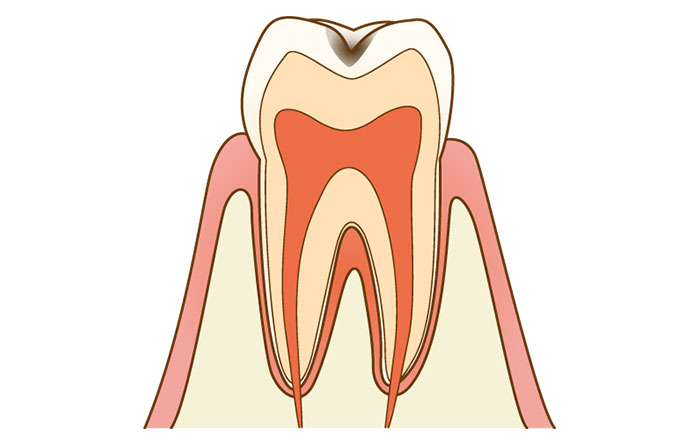

3.C2のむし歯

しみる状態は、一般的にはC2以上の進行具合です。

C2のむし歯は、エナメル質の内部にある、象牙質という部分にまでむし歯が達している状態です。

この段階になると、目視で色がついているのを確認でき、茶色や黒色の穴が空きます。

C2になると、水・お湯・甘いものがしみるなど、自覚症状が出ることがあります。